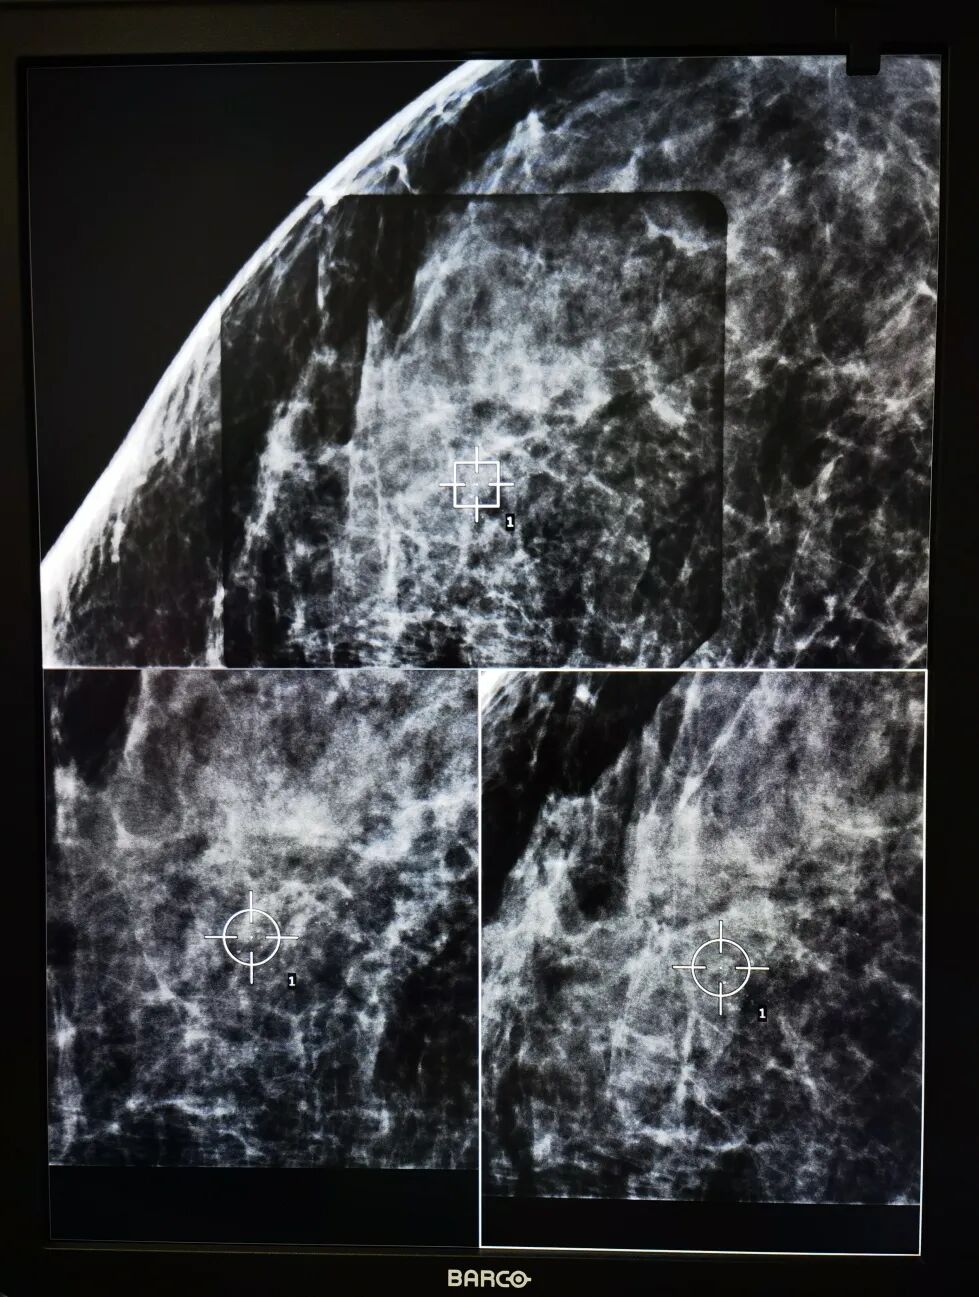

发现乳房肿块或异常,往往是通过物理检查、X线摄片,或其他影像学来辅助诊断。一直以来,传统的乳腺钼靶X线摄影对于各个年龄段女性乳腺病变,尤其是乳腺钙化灶的筛查和诊治都是必不可少的影像学检查;最新的3D数字断层乳腺X线对于40岁以下女性的致密性乳房也同样可以进行精准的断层成像诊断,破解了传统2D钼靶对于致密乳房无法清晰成像的限制,可以最大程度的剖析乳房的异常病灶,若配合X线影像引导下穿刺活检设备可为患者带来最可靠的乳腺X线摄影诊疗技术。

乳腺的数字断层合成影像不同于标准的乳房 X 光检查,就像胸部的 CT 扫描不同于胸部 X 射线一样。试想“球”和“圆”的区别,一个是三维成像,另一个是二维平面的。X线影像引导下的乳腺穿刺活检手术,是一种3D X线数字摄影立体定位成像穿刺活检技术,利用乳房低剂量断层X线摄影结合真空辅助装置和穿刺针活检,用以帮助找到在影像中的异常乳腺病变,在显微镜下检查穿刺组织样本的类型。X线影像引导下的乳腺穿刺活检手术,共比通过手术切取乳腺变异组织活检更微创,皮肤表面几乎无疤痕,可以捕捉到微小钙化和乳腺结构异常的病变,如果发现癌细胞,明确诊断后,医生可以使用病理诊断信息给与患者后续的治疗意见,是一种精准微创的乳腺疾病诊治技术。

X线数字断层摄影立体定位的乳腺穿刺活检需要使用乳腺X线数字摄影机、辅助计算机成像系统、立体定位穿刺针和真空辅助装置,整个过程由乳腺外科医生操作,放射科技师配合,一般半个小时内就可以完成,每一步操作都十分严谨精确,每一例病患选择都有严格的手术适应症。X线数字摄影立体定位的乳腺穿刺活检适用于如下乳房X光影像检查显示的乳腺异常:可疑的肿块;微小的簇状钙化;乳腺组织结构变形;组织变化异常区;新生的钙沉积在曾手术部位。尤其是乳腺钙化借助X线数字摄影立体定位的乳腺穿刺活检是可靠的诊断方法,也是乳房非肿块可疑钙化灶活检的唯一影像学引导定位方式。

上海市交通大学医学院附属同仁医院影像科新近装备了美国进口豪洛捷(HOLOGIC)全数字乳腺X射线摄影系统Digital Mammography X-ray Equipment(Selenia Dimensions),在开展常规乳腺筛查、精准成像诊断同时,乳腺外科团队已利用其精准3D定位优势开展乳腺活检穿刺诊断和治疗。精准+微创:X线影像引导下的乳腺穿刺活检技术让临床怀疑但又未触及的显示在乳腺X线摄影中的乳腺病灶无处遁形。